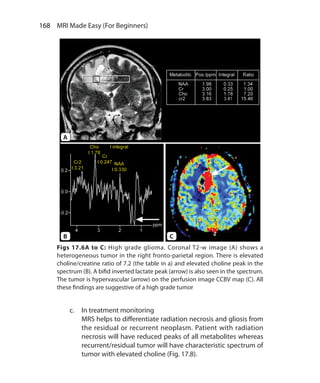

4838/24, Ansari Road, Daryaganj